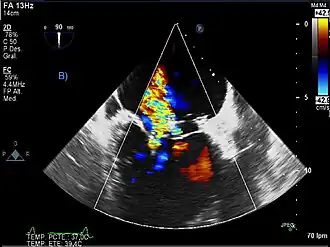

Como mejoría, la ecografía Doppler se basa en el efecto del mismo nombre. Cuando el objeto que refleja las ondas de ultrasonido se mueve, cambia la frecuencia de los ecos, aumentando la frecuencia si se mueve hacia la sonda y disminuyéndola si se aleja de la sonda. Cuánto cambia la frecuencia depende de cómo de rápido se mueva el objeto. La ecografía Doppler mide el cambio en la frecuencia de los ecos para calcular lo rápido que se mueve un objeto. Se utiliza principalmente para medir la velocidad del flujo sanguíneo a través del corazón y las arterias principales. Veremos a continuación su aplicación en cardiología, principalmente.

Cardiología

Dentro de este ámbito se ubica la ecocardiografía que también permite obtener una presentación en forma de gama de colores acordes con la velocidad de un fluido, como la sangre. esta técnica tiene especial incidencia en: